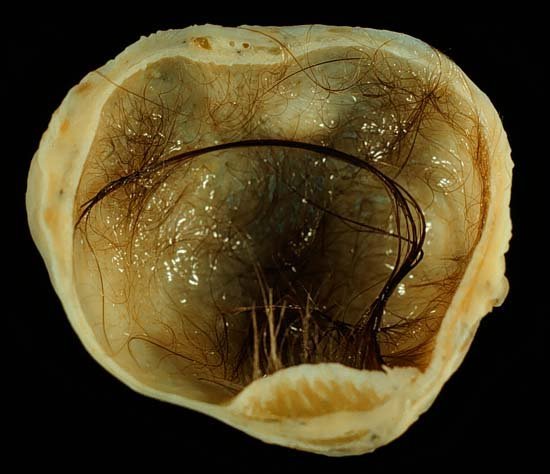

ซีสต์มีหลายอย่าง แต่ที่เห็นในภาพเรียก Dermoid Cyst เป็นซีสต์ที่ผิดปกติ เกิดขึ้นในหญิงอายุน้อย เส้นผ่านศูนย์กลางโตได้ถึง 6 นิ้ว ซีสต์ประเภทนี้จะมีส่วนประกอบคล้ายเซลล์ผิวหนังอยู่ด้านใน เช่นเส้นผม ขน ฟัน กระดูก ลูกตา

เดอร์มอยด์ซีสต์ (Dermoid cyst หรือ Teratoma) เกิดจากเซลล์ผิวหนังที่จัดวางอยู่ผิดตำแหน่งตั้งแต่พัฒนาการขั้นแรกของทารกในครรภ์ มักพบเส้นผม เล็บ กระดูก ไขมันอยู่ภายใน